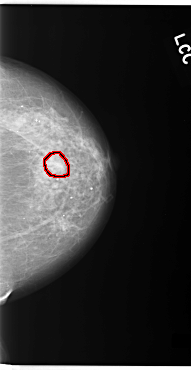

C_0093_1.LEFT_MLO

LEFT_MLO LINES 5840 PIXELS_PER_LINE 3104 BITS_PER_PIXEL 12 RESOLUTION 50 OVERLAY

FILE: C_0093_1.LEFT_MLO.OVERLAY

TOTAL_ABNORMALITIES 1

ABNORMALITY 1

LESION_TYPE CALCIFICATION TYPE AMORPHOUS DISTRIBUTION CLUSTERED

ASSESSMENT 5

SUBTLETY 4

PATHOLOGY MALIGNANT

TOTAL_OUTLINES 1

BOUNDARY